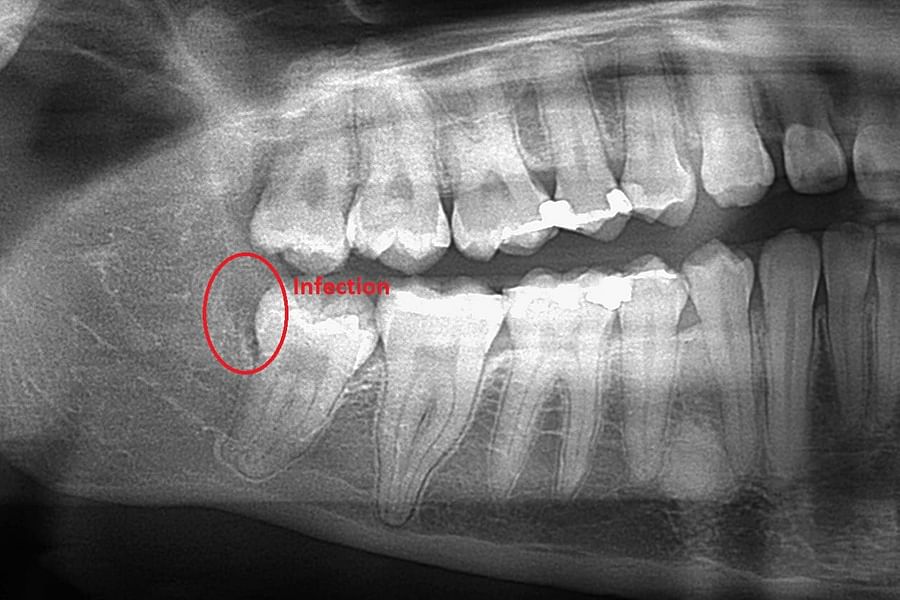

Dental X-rays are more than just tools for diagnosing cavities; they provide a comprehensive view of your oral health status. By allowing dentists to detect problems before they become severe, these images can save patients time, money, and discomfort in the long run. Early detection through modern imaging technology can reveal hidden decay between teeth, bone loss due to gum disease, or even cysts and tumors that are not visible during a standard exam.

- Tumors - Spotting abnormal growths or cysts within the jawbone.

- Bone Loss - Evaluating the extent of bone loss associated with osteoporosis or other conditions.

Despite the myths surrounding dental x-rays, they play an integral role in preventative dentistry. X-rays allow dentists to detect issues that are not visible during a standard oral exam. This includes early signs of decay between teeth, problems below the gum line, and changes in bone density that could indicate periodontal disease. By identifying these problems early, fundamental dental treatments can be administered promptly, saving patients from more extensive and costly procedures down the line.